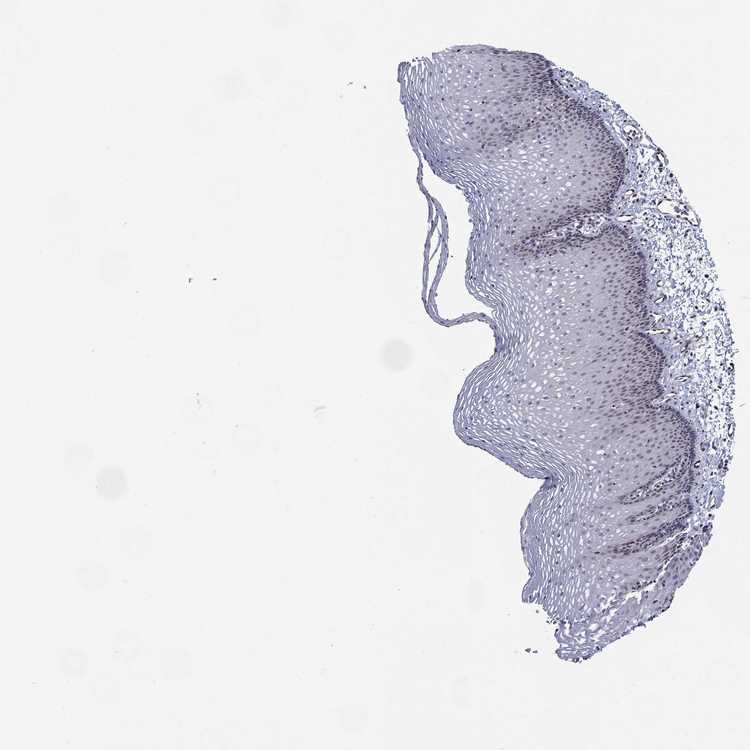

ESOPHAGUS - Antibody stainingi

Antibody staining in the annotated cell types in the current human tissue is reported as not detected, low, medium, or high, based on conventional immunohistochemistry profiling in selected tissues. This score is based on the combination of the staining intensity and fraction of stained cells.

Each image is clickable and will lead to virtual microscopy that enables deeper exploration of all samples and also displays staining intensity scores, fraction scores and subcellular localization as well as patient and tissue information for each sample.

Antibody HPA077591

Squamous epithelial cells Not detected